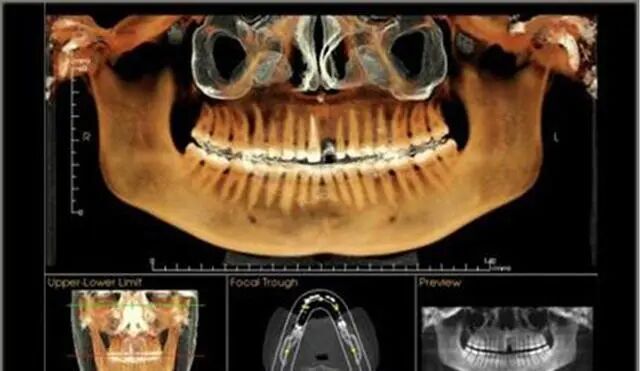

不过在做种植牙手术前,需要由种植医生进行口腔检查,拍摄常规CT和做血液常规检查,才可以确定是否适合种植牙。